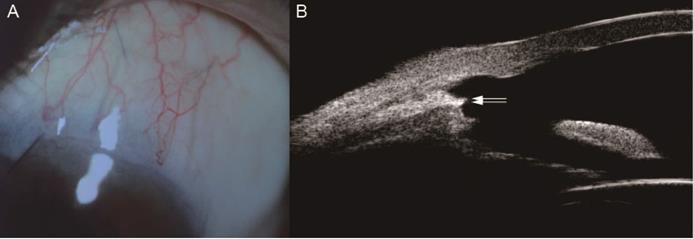

BCVA at 2 year post-operatively was 0.2 (0~3), which showed no significant difference compared with baseline (Z=-1.223, P=0.221). According to IBAGS, 10 (18.9%) eyes' blebs were graded as E1H1 1 week postoperatively. One month after the operation, 2 (3.8%) eyes' blebs were graded as E0H1. At 3 months post-operatively, all patients had no obvious blebs (E0H0) (Figure 3). Intraoperative complications included hyphema in 15 eyes (28.3%), which was controlled by oppression hemostasis with a viscoelastic agent. Four eyes (7.5%) had postoperative hyphema and 2 eyes (3.8%) had anterior chamber exudation, which was absorbed within 7 days after conservative treatment. Three eyes (5.7%) had transiently elevated IOP in post-operative 1 month, which was controlled after topical use of glaucoma medications and acupuncture separation. No blebitis, shallow anterior chamber, choroidal detachment and endophthalmitis were observed.

Figure 3

The Filtration Bleb of One PACG Patient 3 Months after Trabeculo-Canalectomy. A Anterior segment photograph of the filtration bleb; B Ultrasound biomicroscopy of the filtration bleb; PACG, Primary angle-closure glaucoma; White arrow, the inner wall of Schelemn's canal.

We observed a significant reduction in IOP at 7 postoperative time points (Figure 2). The complete success rate of trabeculo-canalectomy at 1, 3, 6, 12 and 24 months was 92.5%, 86.8%, 94.3%, 92.5% and 90.6% respectively (Table 2), which showed good therapeutic effects compared with previous literature [10-12]. International and domestic studies reported that IOP drop rate of trabeculectomy combined with anti-metabolizing drugs or releasable sutures in PACG patients was 44-70% [13]. The success rate of trabeculectomy at 6 months postoperatively was 72%-91% [14] and 54-65% at 3 years postoperatively [15-17], which depends on follow-up time and the criteria used to define the successful outcome. In our study, no visible filtering blebs were observed in all eyes 3 months post-operatively (Figure 3), which fully demonstrated the efficacy of internal Schlemm's canal drainage. Since trabeculo-canalectomy is non-bleb dependent, the success rate may not be affected by external wound healing, despite the long-term outcomes need more cases and further observation.